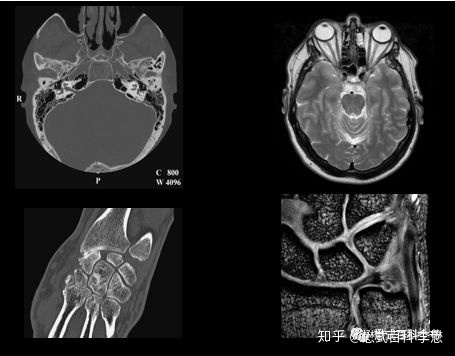

如上图所示,左边为CT图像,右边为磁共振图像。CT图像中,头颅可以看到,骨头(骨组织)由于密度高,在图像上是最亮的(最白的);右边的图,是磁共振T2WI,在T2WI中,液体和脂肪是高信号(白色,亮),而骨头(骨皮质)是低信号(黑色,暗)。同样,下图中,CT的腕关节片,骨组织密度高,所以反映在图片上式亮的(白);而磁共振图,同样是T2WI,结合了脂肪抑制,则骨组织信号是低的,反映在图中是黑的(暗)。

我们再来看一例,温习一下。左边是CT图像,我们可以看到,图像中越亮的(越白的)代表组织密度越高的。在CT图像中,我们发现,骨组织密度高,图像中越亮。另外,这张图,我们还发现肾皮质,膀胱是亮的,不是因为肾皮质和膀胱组织(里面的液体)密度高,而是因为注射了对比剂(CT造影剂)。我们还组织,皮下的脂肪组织,在CT图像中,是黑的,代表脂肪组织密度不高(脂肪密度低于水,所以脂肪能够浮在水面上)。右边的图是磁共振图像,也是一个T2WI图,在这个图像中,脂肪和液体信号强度是高的,反映过了就是脂肪组织和液体在T2WI磁共振图像中变现为亮的。那么图中,非常清楚,皮下脂肪组织是非常亮的,另外骨头也是亮的(因为骨髓里面含有脂肪组织)。

由于CT图像是直接反映组织对X线的吸收衰减,跟组织的密度是相关的,所以,CT图像在诊断结石或者钙化的时候是非常好的。因为一般来说,结石或者钙化都是高密度,在CT图像上会表现为点状或者其他形状的亮点,所以比较容易检出。

而磁共振图像,并不是反映组织密度的。钙化由于其特殊物质组成,在磁共振的各种序列上,一般表现为低信号,也就是图像中的暗点,所以不容易显示。这也是磁共振相对CT的一个劣势,对钙化显示(检出)差。